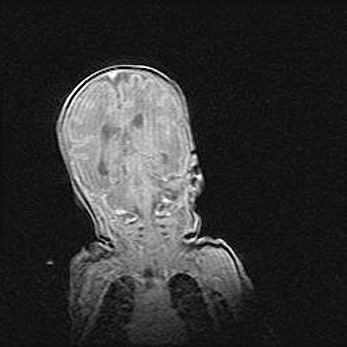

Множественные кисты обоих полушарий головного мозга, наибольшая из них в правой затылочной области. Ассиметричная атрофическая гидроцефалия.

Возраст: 7 месяцев

Вес: 5660 г

Пол: мужской

Окружность головы: 41,5 см

Срок гестации: 28-29 недель

Кисты головного мозга развиваются в результате многоочаговых некрозов вещества мозга и возникают вследствие перенесенной перинатальной инфекции, менингитов, энцефалитов, асфиксии, родовой травмы, расстройств мозгового кровообращения различного генеза. Образованию кист в веществе головного мозга плодов и новорожденных способствуют такие факторы, как высокое содержание в нем воды, недостаточная (или отсутствие) миелинизация и слабая астроглиальная реакция на повреждение.

Кисты могут сочетаться с гидроцефалией и другими поражениями головного мозга.